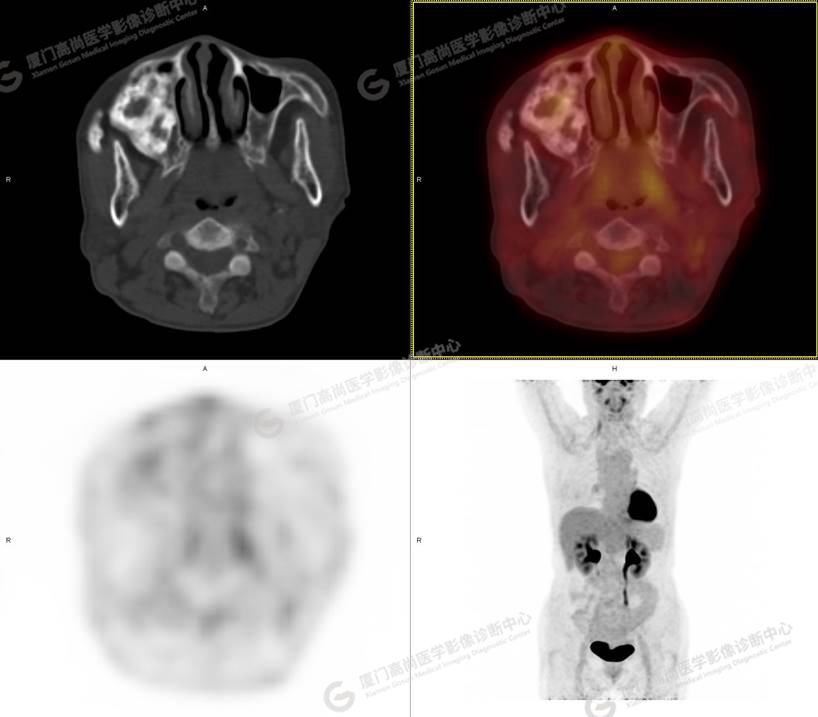

圖1

圖2

圖3

圖4

PET/CT所見:右側(cè)上頜骨、右側(cè)顴骨及右側(cè)額骨骨質(zhì)膨脹,其內(nèi)密度不均勻性增高,部分放射性攝取輕微增高,SUVmax 2.27。